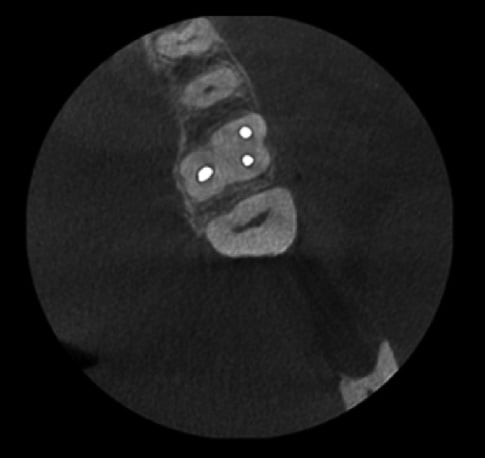

Bez usuwania artefaktów

Z użyciem algorytmu usuwania artefaktów Planmeca ARA

Metalowe uzupełnienia lub wypełnienia w zębach pacjenta mogą powodować cienie lub smugi na obrazie CBCT. Inteligentny system Planmeca ARA™ skutecznie usuwa te artefakty z obrazów Planmeca ProMax® 3D.